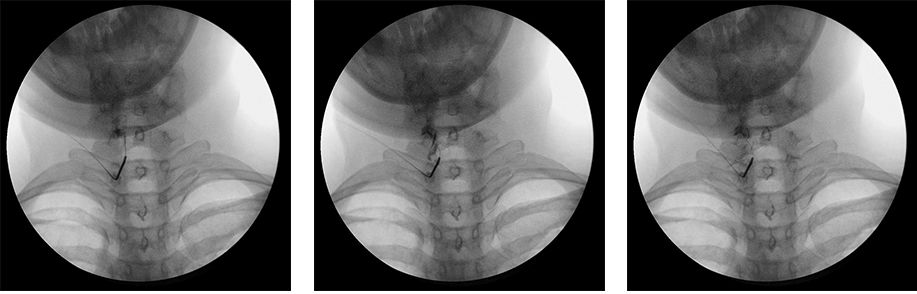

경막외 감압술은 척추 질환의 대표적인 비수술 치료법으로 작은 관을 이용하여 지름 1~2mm 정도의 얇은 관을 꼬리뼈쪽으로 삽입한 후

디스크나 신경의 염증이 있는 부위에 약물을 투여하는 치료법입니다.

신경의 압박을 풀어주고 염증과 유착을 제거하여 신경 주변의 혈액순환을 개선하는 시술 방법입니다.